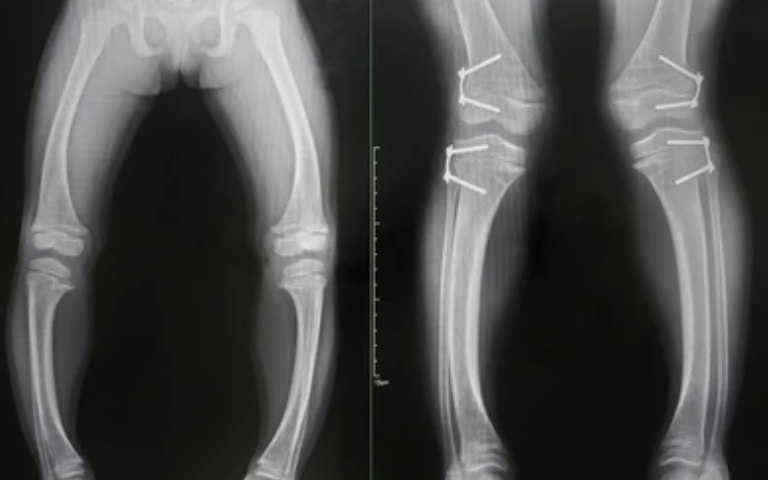

Bone deformities can involve abnormal angulation, shortening, rotation, or curvature of bones, leading to pain, joint stress, and impaired mobility. Common causes include congenital conditions, growth plate injuries, malunited fractures, bone infections, and metabolic disorders. A detailed clinical examination and imaging studies help determine the exact nature and severity of the deformity, allowing precise treatment planning.

Treatment depends on the type, location, and impact of the deformity on movement and joint health. In mild cases, observation or bracing may be sufficient, while more significant deformities may require surgical correction. Corrective procedures aim to realign the bone, restore limb length, and improve joint function. Each treatment plan is tailored to the patient’s age, functional needs, and overall health.